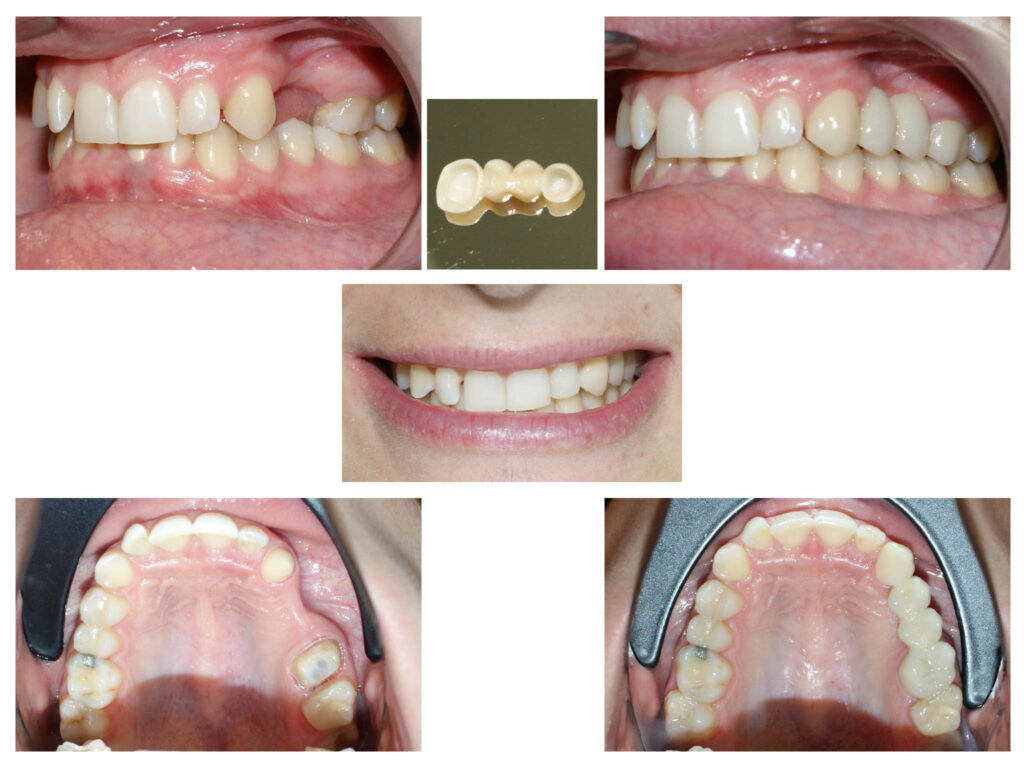

Dinții nanici își găsesc la noi rezolvare estetică și minim invazivă – coroniță cu preparare minimă ghidată

Coroniță zirconiu pe incisivul central cu integrarea estetică